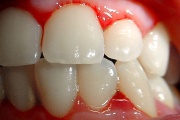

Äge krooniline gingiviit

igemete veritsus kroonilise gingiviidiga patsiendil

Gingiviit ehk igemepõletik